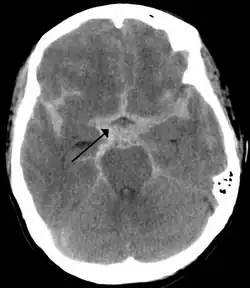

As first postulated by Harvey Cushing, raised intracranial pressure is the primary cause of the Cushing reflex.[3] Furthermore, continued moderate increases in cranial pressure allows for the Cushing reflex to occur. In contrast, rapid and dramatic pressure rises do not allow for the mechanism of the reflex to sufficiently take place.[12] Elevated intracranial pressure can result from numerous pathways of brain impairment, including: subarachnoid hemorrhages, ischemia, meningitis, trauma, including concussions, hypoxia, tumors, and stroke. In one study, it was confirmed that raised ICP due to subarachnoid hemorrhaging causes mechanical distortion of the brainstem, specifically the medulla. Due to the mechanism of the Cushing reflex, brainstem distortion is then swiftly followed by sympathetic nervous system over activity.[13] In addition, during typical neurosurgical procedures on patients, especially those involving neuroendoscopic techniques, frequent washing of the ventricles have been known to cause high intracranial pressure.[7] The Cushing reflex can also result from low CPP, specifically below 15 mmHg.[14] CPP normally falls between 70-90 mmHg in an adult human, and 60-90 mmHg in children.